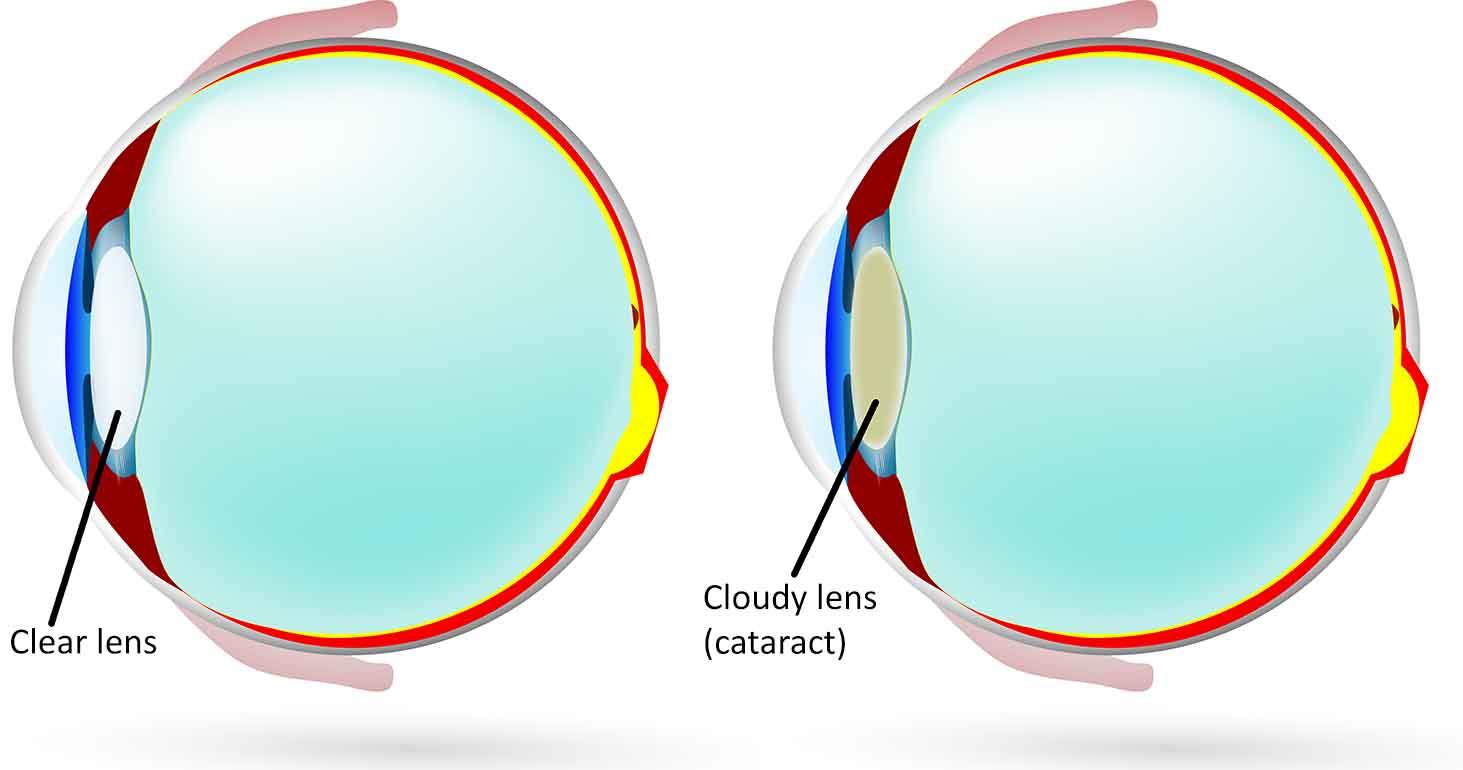

白內障是因水晶體變混濁,遮蔽原本應進入眼球的光線,導致視力模糊。

白內障是因水晶體變混濁,遮蔽原本應進入眼球的光線,導致視力模糊,3大症狀包括:視力模糊、畏光、近視或散光度數突然增加。若更換眼鏡後仍無法有效改善視力,要當心恐是白內障徵兆。白內障高風險族群包括老年人、近視度數大於600度之高度近視者、糖尿病患、虹彩炎患者、眼睛受過傷之民眾。以往白內障患者多數為老年人,但隨著大眾深近視的比例增加、糖尿病年輕化,白內障有年輕化趨勢。

白內障是不可逆的,雖然市面上有多種眼藥或是保養食品,但效果僅可能延緩病程發展,唯一直接有效的治療方法就是進行手術。

白內障是不可逆的,唯一直接有效的治療方法就是進行手術。